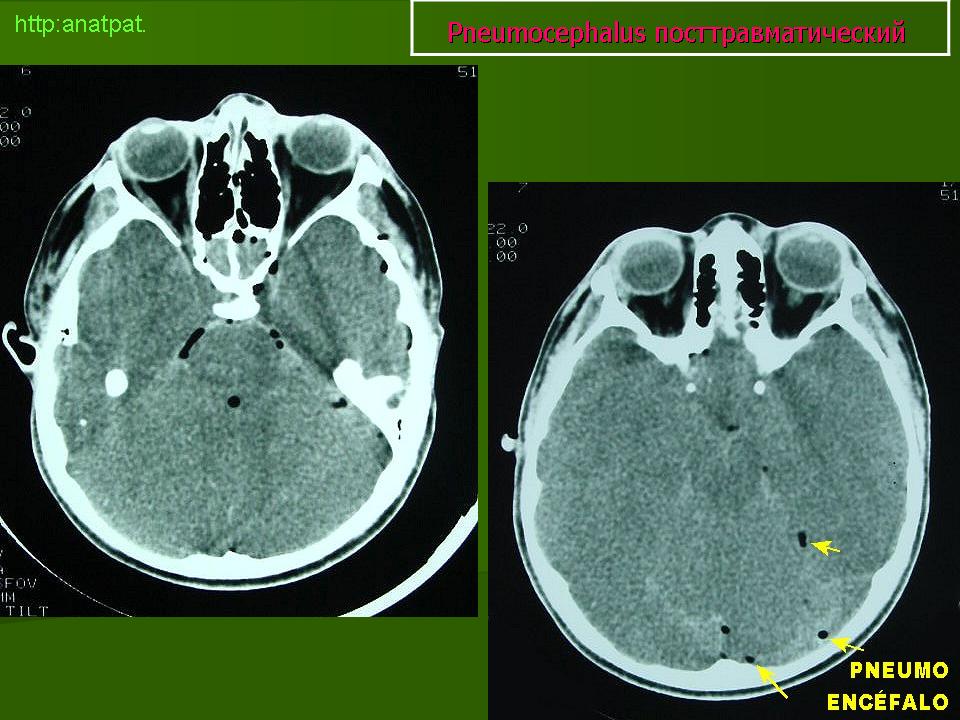

A) NEUMOCÉFALO POSTRAUMÁTICO: Es una complicación muy grave de un traumatismo craneoencefálico y se produce por fractura de la pared de los senos paranasales o de la base del cráneo. Cuando una persona sufre un accidente muy violento, como sucede en los de tráfico, se producen múltiples fracturas de cráneo. Si alguna rompe la pared de los senos paranasales y una esquirla ósea desgarra la duramadre, el aire penetra al interior del cráneo y se acumula en cualquiera de los espacios intracraneales, aunque fundamentalmenteen el subaracnoideo. En el topograma preliminar de una TC se aprecia una imagen hipodensa que representa el gas depositado en el espacio subaracnoideo frontal (flechas) porque al realizar la exploración en decúbito supino el aire asciende hacia las partes más elevadas de la cavidad craneal. (Figura 1).

FIGURA 1) Neumocéfalo postraumático. El aire, que ha penetrado en el espacio subaracnoideo de las cisternas basales como consecuencia de la fractura del techo del seno esfenoidal y de la duramadre, asciende por gravedad al espacio subaracnoideo frontal, donde forma un nivel (flechas)